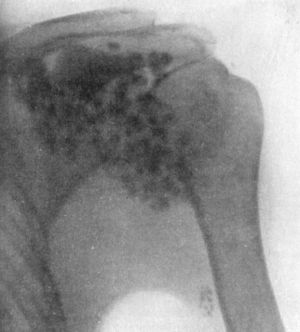

103.Arthropathy of Shoulder in Syringomyelia203

104.Radiogram of Specimen of Arthropathy of Shoulder in Syringomyelia204

105.Radiogram showing Multiple partially Ossified Cartilaginous Loose Bodies in Shoulder-joint205